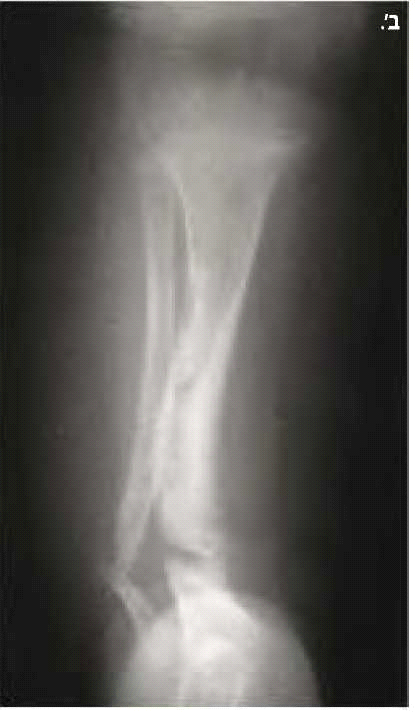

בנוירופיברומטוזיס מסוג 1 קיימות פגיעות שלדיות רבות. המעורבות הגרמית היא לרוב קלה ולעתים אף מהווה קריטריון אבחנתי למחלה, כמו למשל דיספלזיה (Dysplasia) של עצם היתד (Sphenoid) (תמונה 6) או אי חיבור (Pseudoarthrosis) של עצם השוקה (Tibia) (תמונה 7). בעיות שכיחות יותר הן קומה נמוכה (כ-30%) ועקמת (כ-10%). לעתים נצפים מקרים קשים של עקמת ועקשת (Kyphoscoliosis) המחמירים במהלך החיים ומסכנים את תפקוד הריאות והלב ודורשים התערבות ניתוחית (תמונה 8). כ-50% מהמבוגרים עם נוירופיברומטוזיס מסוג 1 מפתחים ירידה בצפיפות העצם (Osteoporosis) וזקוקים לאבחון וטיפול תרופתי בהתאם.

- נגעים גרמיים אופייניים כגון דיספלזיה של עצמות היתד בגולגולת או אי חיבור של עצם השוקה